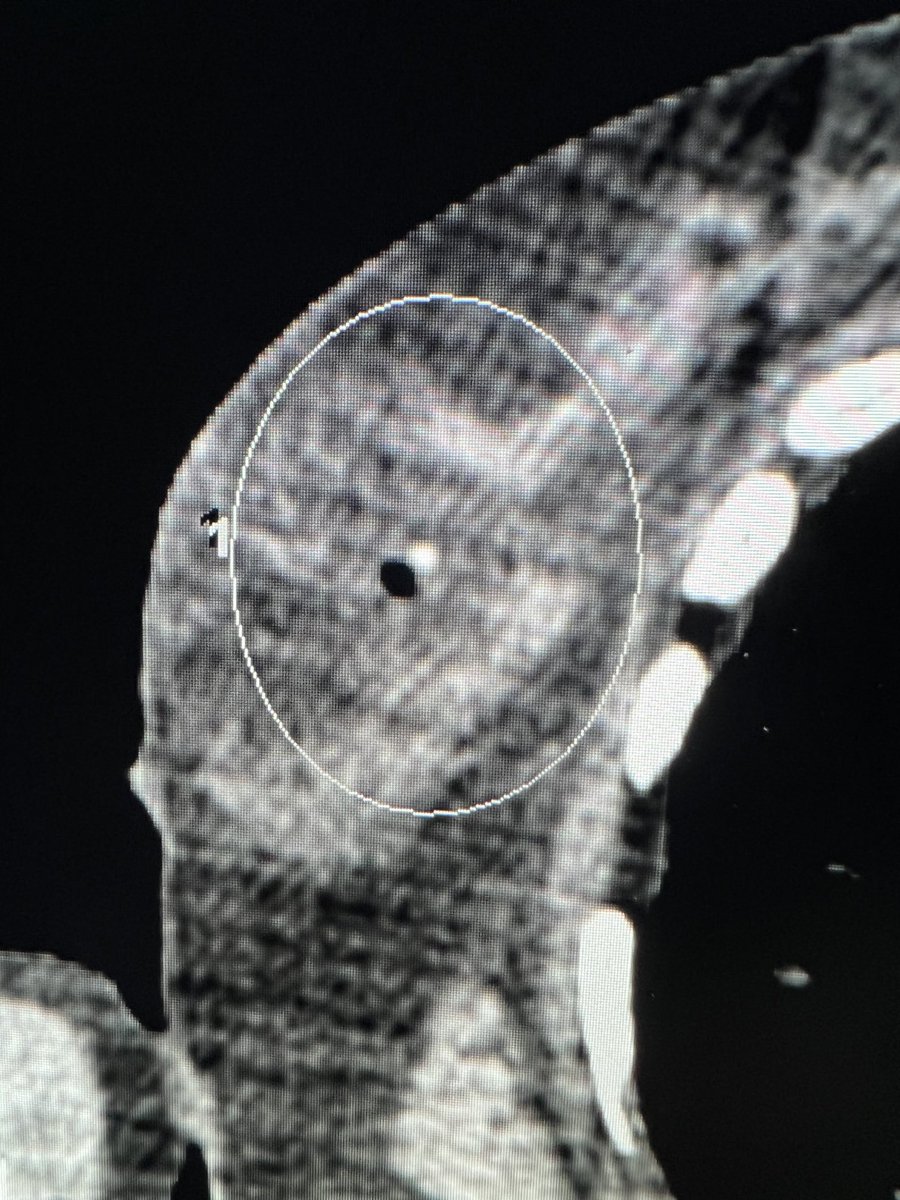

#breastcancer #Cryoablation North York General Advanced age, 6mm malignancy with HydroMark clip, tumour board recommended cryo. ICE 1.5mm 17G, protective hydrodissection, CT shows clip centrally in ice ball. Posted w permission Canadian Association for Interventional Radiology #IRad #MedEd UofT Medical Imaging thx Patrick Kennedy assisting

#breastcancer #Cryoablation <a href="/NYGH_News/">North York General</a> Advanced age, 6mm malignancy with HydroMark clip, tumour board recommended cryo. ICE 1.5mm 17G, protective hydrodissection, CT shows clip centrally in ice ball. Posted w permission <a href="/CAIRweb/">Canadian Association for Interventional Radiology</a> #IRad #MedEd <a href="/UofTMedIm/">UofT Medical Imaging</a> thx <a href="/DrPatKennedy/">Patrick Kennedy</a> assisting